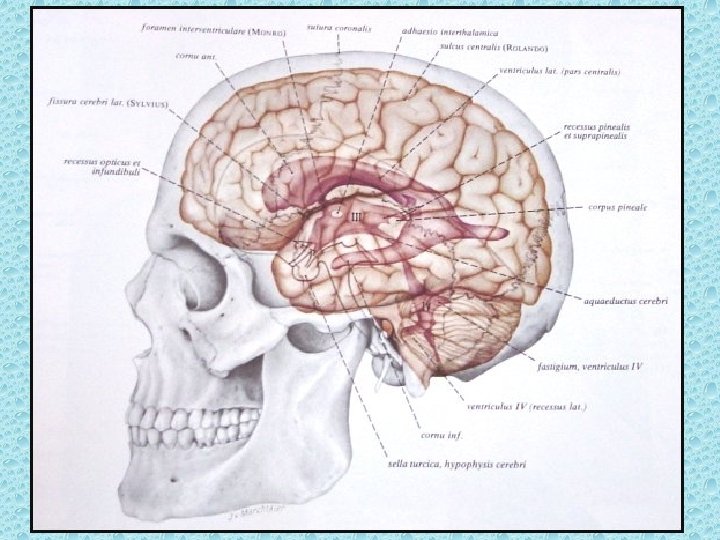

VENTRİKÜLLER • Lateral ventriküller: frontal, oksipital ve temporal hornlar, korpus ve atrium • Foramen monro • 3. Ventrikül • Akuaduktus silvii • 4. Ventrikül • Foramen Lucka (çift) ve magendi (tek)

KAFA İÇİNİ BESLEYEN ARTERLER • Bilateral karotid sistem: İnternal karotid arter - A. oftalmika, a. kommunikans posterior, a. koroidea, a. serebri anterior ve media • Vertebrobaziler sistem: Vertebral arterler ve baziller arterlerden oluşur - A. Serebellaris posterior inferior (pica), anterior inferior (aica), a. serebellaris superior, a. serebri posterior

WILLIS POLİGONU • • • Bilateral internal karotid arter Bilateral anterior serebral arter Anterior kommunikan arter Bilateral post. Kommunikan arter Bilateral post serebral arter